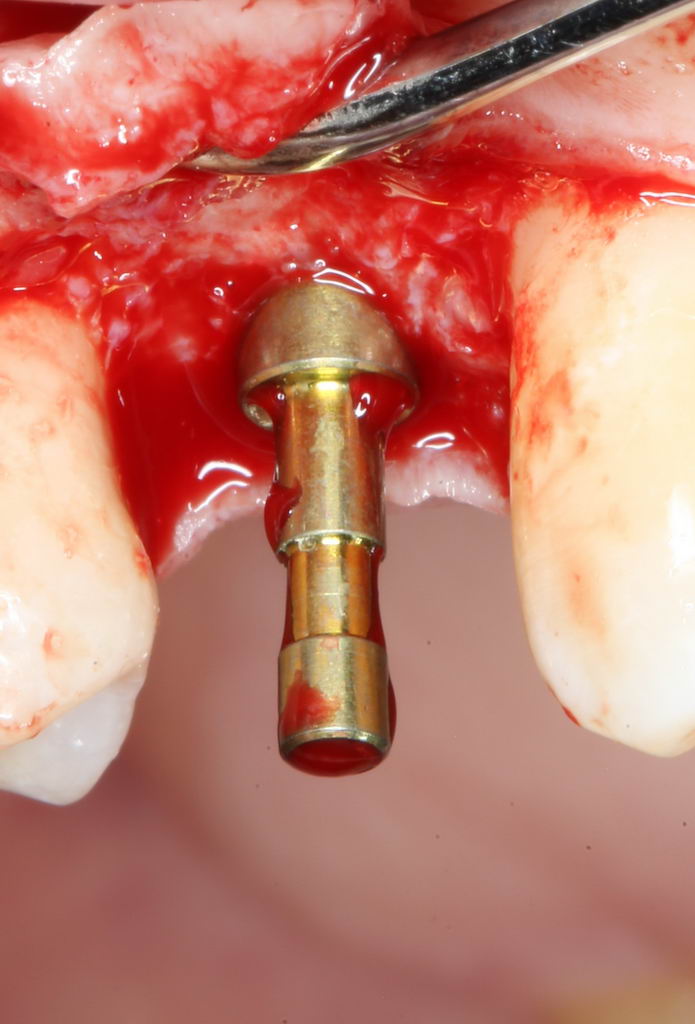

Больше нам абатмент TempBase не нужен, мы его убираем:

Без абатмента можно оценить позиционирование имплантата по глубине погружения. Напомню, что XiVE — это субгингивальная имплантационная система, поэтому ортопедическая платформа имплантата должна находиться на уровне костной ткани. Что и было выполнено в нашем случае.

И, коль всё в порядке, переходим к следующему этапу операции — установке формирователя десны.